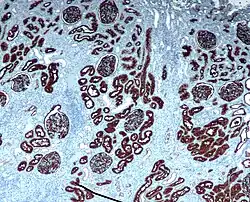

Neprilysin immunohistochemical staining of normal kidney.

Neprilysin is also associated with other biochemical processes, and is particularly highly expressed in kidney and lung tissues. Inhibitors have been designed with the aim of developing analgesic and antihypertensive agents that act by preventing neprilysin's activity against signaling peptides such as enkephalins, substance P, endothelin, and atrial natriuretic peptide.[13][14]